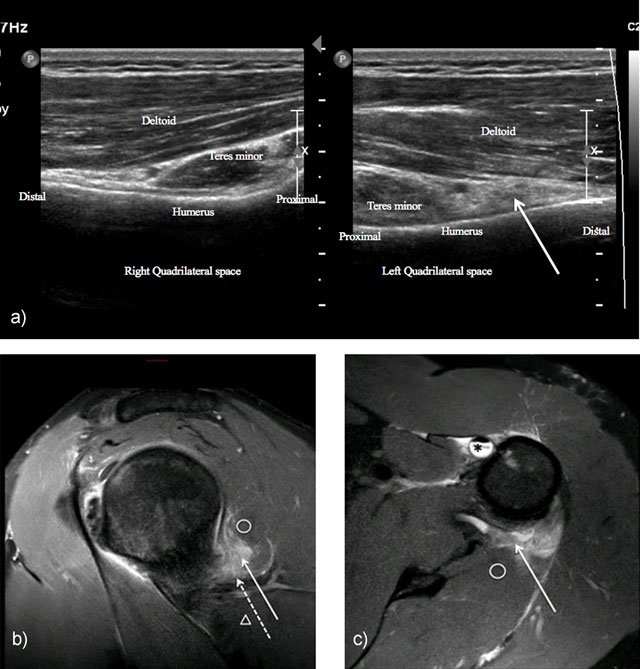

Figure 4

Neuropathy of axillary nerve after skiboard fall leading to injury of the shoulder capsule. Ultrasound showed infiltration of the axillary nerve (dashed arrow) in quadrilateral space (solid arrow) compared to normal side (4a = FIGURE 10 uploaded online manuscript), confirming by sagittal (4b = FIGURE 11 uploaded online manuscript), axial (4c = FIGURE 12 uploaded online manuscript) Proton Density with Fat Saturation MRI images. Note the concomitant Biceps brachii tendon injury (star). Teres minor muscle (circle) – Teres major muscle (arrowhead).